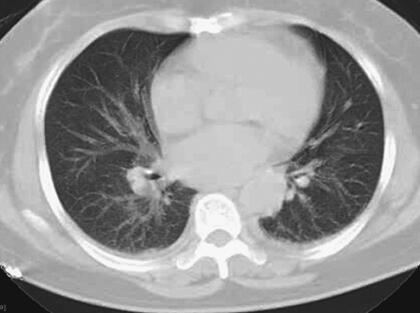

患者,女性,59岁。因“发热8天,上腹部隐痛、腹泻伴胸闷7天”于2011年7月8日入院。患者8天前出现发热,39.5℃,无畏寒、寒战,在当地卫生院予输液治疗(具体不详),症状未好转。7天前出现上腹部隐痛、腹泻,日约4~5次,黄色稀便,伴胸闷,遂就诊于当地镇医院,心电图检查正常,拟“中暑”,予针灸等治疗后无好转。2天前就诊于当地县人民医院,查血常规:WBC 8.4×109/L,N 89.2%,Hb 102g/L,PLT 92×109/L;肥达反应阴性;肝功能:ALT 104IU/L,AST 144IU/L,TP 55g/L,ALB 27g/L;腹部CT:脂肪肝,脾肿大;胸部CT:两肺少许炎症,左侧可疑少许胸腔积液,拟败血症,中毒性肝炎,伤寒住院治疗;期间体温波动于38~39℃,血压波动于80/50~90/60mmHg,予多巴胺[6.0μg/(kg·min)]升压,予亚胺培南-西司他汀钠联合头孢曲松抗感染治疗,病情无好转,仍有发热、腹泻、上腹部隐痛不适,并出现尿量减少、血肌酐升高。于7月8日转笔者医院急诊,测血压[多巴胺6.0μg/(kg·min)维持]89/55mmHg,血常规:WBC 10.28×109/L,N 89.4%;Lac 2.3mmol/L,CRP>90.0mg/L,Cr 141μmol/L,cTnI 6.02μg/L,BNP 577pg/ml;胸腹部CT:两下肺背侧散在炎症,两侧胸腔少量积液,慢肝样病变,胆囊结石(图1、图2);腹部B超:脂肪肝,脾偏大,拟发热待查,心肌炎?感染性休克?,予补液、亚胺培南-西司他汀钠控制感染,多巴胺升血压,为进一步治疗拟上述诊断收入急诊重症监护病房。既往史:40年前发现胆囊结石。

图2 胸腹部CT:脾肿大(7月8日)

关于恙虫病的肺部改变报道较多。有59%~72%的恙虫病患者可有肺部表现,胸部CT表现可以有磨玻璃影、纵隔淋巴结肿大、小叶间隔增厚、胸腔积液、肺门淋巴结肿大,间质增厚、实变,小叶中心性结节。恙虫病可伴有急性呼吸窘迫综合征(ARDS),是一种少见但很严重的并发症。年龄大、血小板减少、早期肺炎(出现呼吸窘迫前2天,胸片上出现浸润征象)均是ARDS的诱发因素。该患者表现为呼吸促,胸部CT表现为双肺纹理增多、增粗,两下肺背侧见斑片样高密度影,边界模糊;两侧少量胸腔积液,氧合指数<200,考虑并发ARDS。